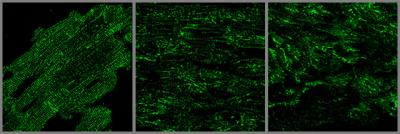

JP2 protein is critical to the normal organization of an important component of heart muscle membrane network called Transverse-tubules or T-tubules. These T-tubules are essential for transmitting the electrical and chemical signals that make a heart beat.

The UI study shows that increased density of microtubules results in abnormal localization of JP2 away from the T-tubule sites to the periphery of the heart cell. The researchers show that this abnormal distribution pattern is also seen in animal models of heart failure and in failing human heart muscle.